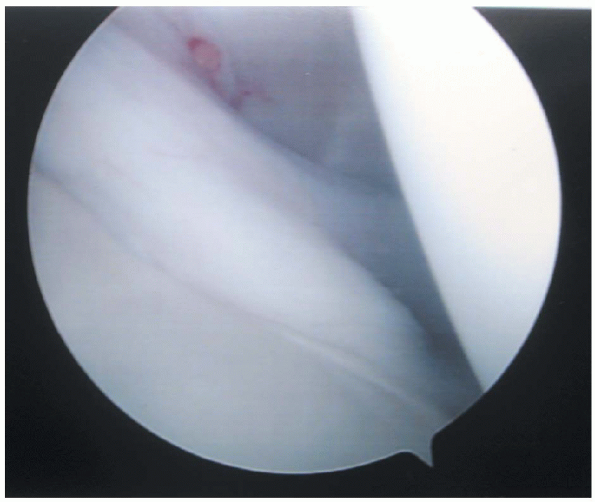

FIGURE 1-4.

The most superior aspects of the subscapularis tendon can be examined during glenohumeral arthroscopy. This “rolled edge” of the tendon can be observed in the anterior aspect of the shoulder. The tendon’s lateral margin can be seen entering the glenohumeral joint through the subscapular recess or bursa. Occasionally, the middle glenohumeral ligament may obscure vision of the subscapularis tendon. A healthy tendon should be free of any fraying or adhesions to surrounding capsular tissues and translate freely with internal and external rotation of the humeral head. |

can be examined during glenohumeral arthroscopy. This region of the

tendon, commonly referred to as the “rolled edge” of the tendon because

of its thickness in this region can be observed in the anterior aspect

of the shoulder (Fig. 1-4). The tendon can be

seen entering the glenohumeral joint through the subscapular recess or

bursa. The bursa lies between the superior and middle glenohumeral

ligaments. Occasionally, the middle glenohumeral ligament may obscure

vision of the subscapularis tendon or even appear to blend with it,

because the ligament lies posterior to the tendon. Differentiation is

based on the tendon’s fibers running perpendicular to the

long

axis of the glenoid, and the ligament runs more obliquely. A healthy

tendon should be free of any fraying or adhesions to surrounding

capsular tissues and translate freely with internal and external

rotation of the humeral head.